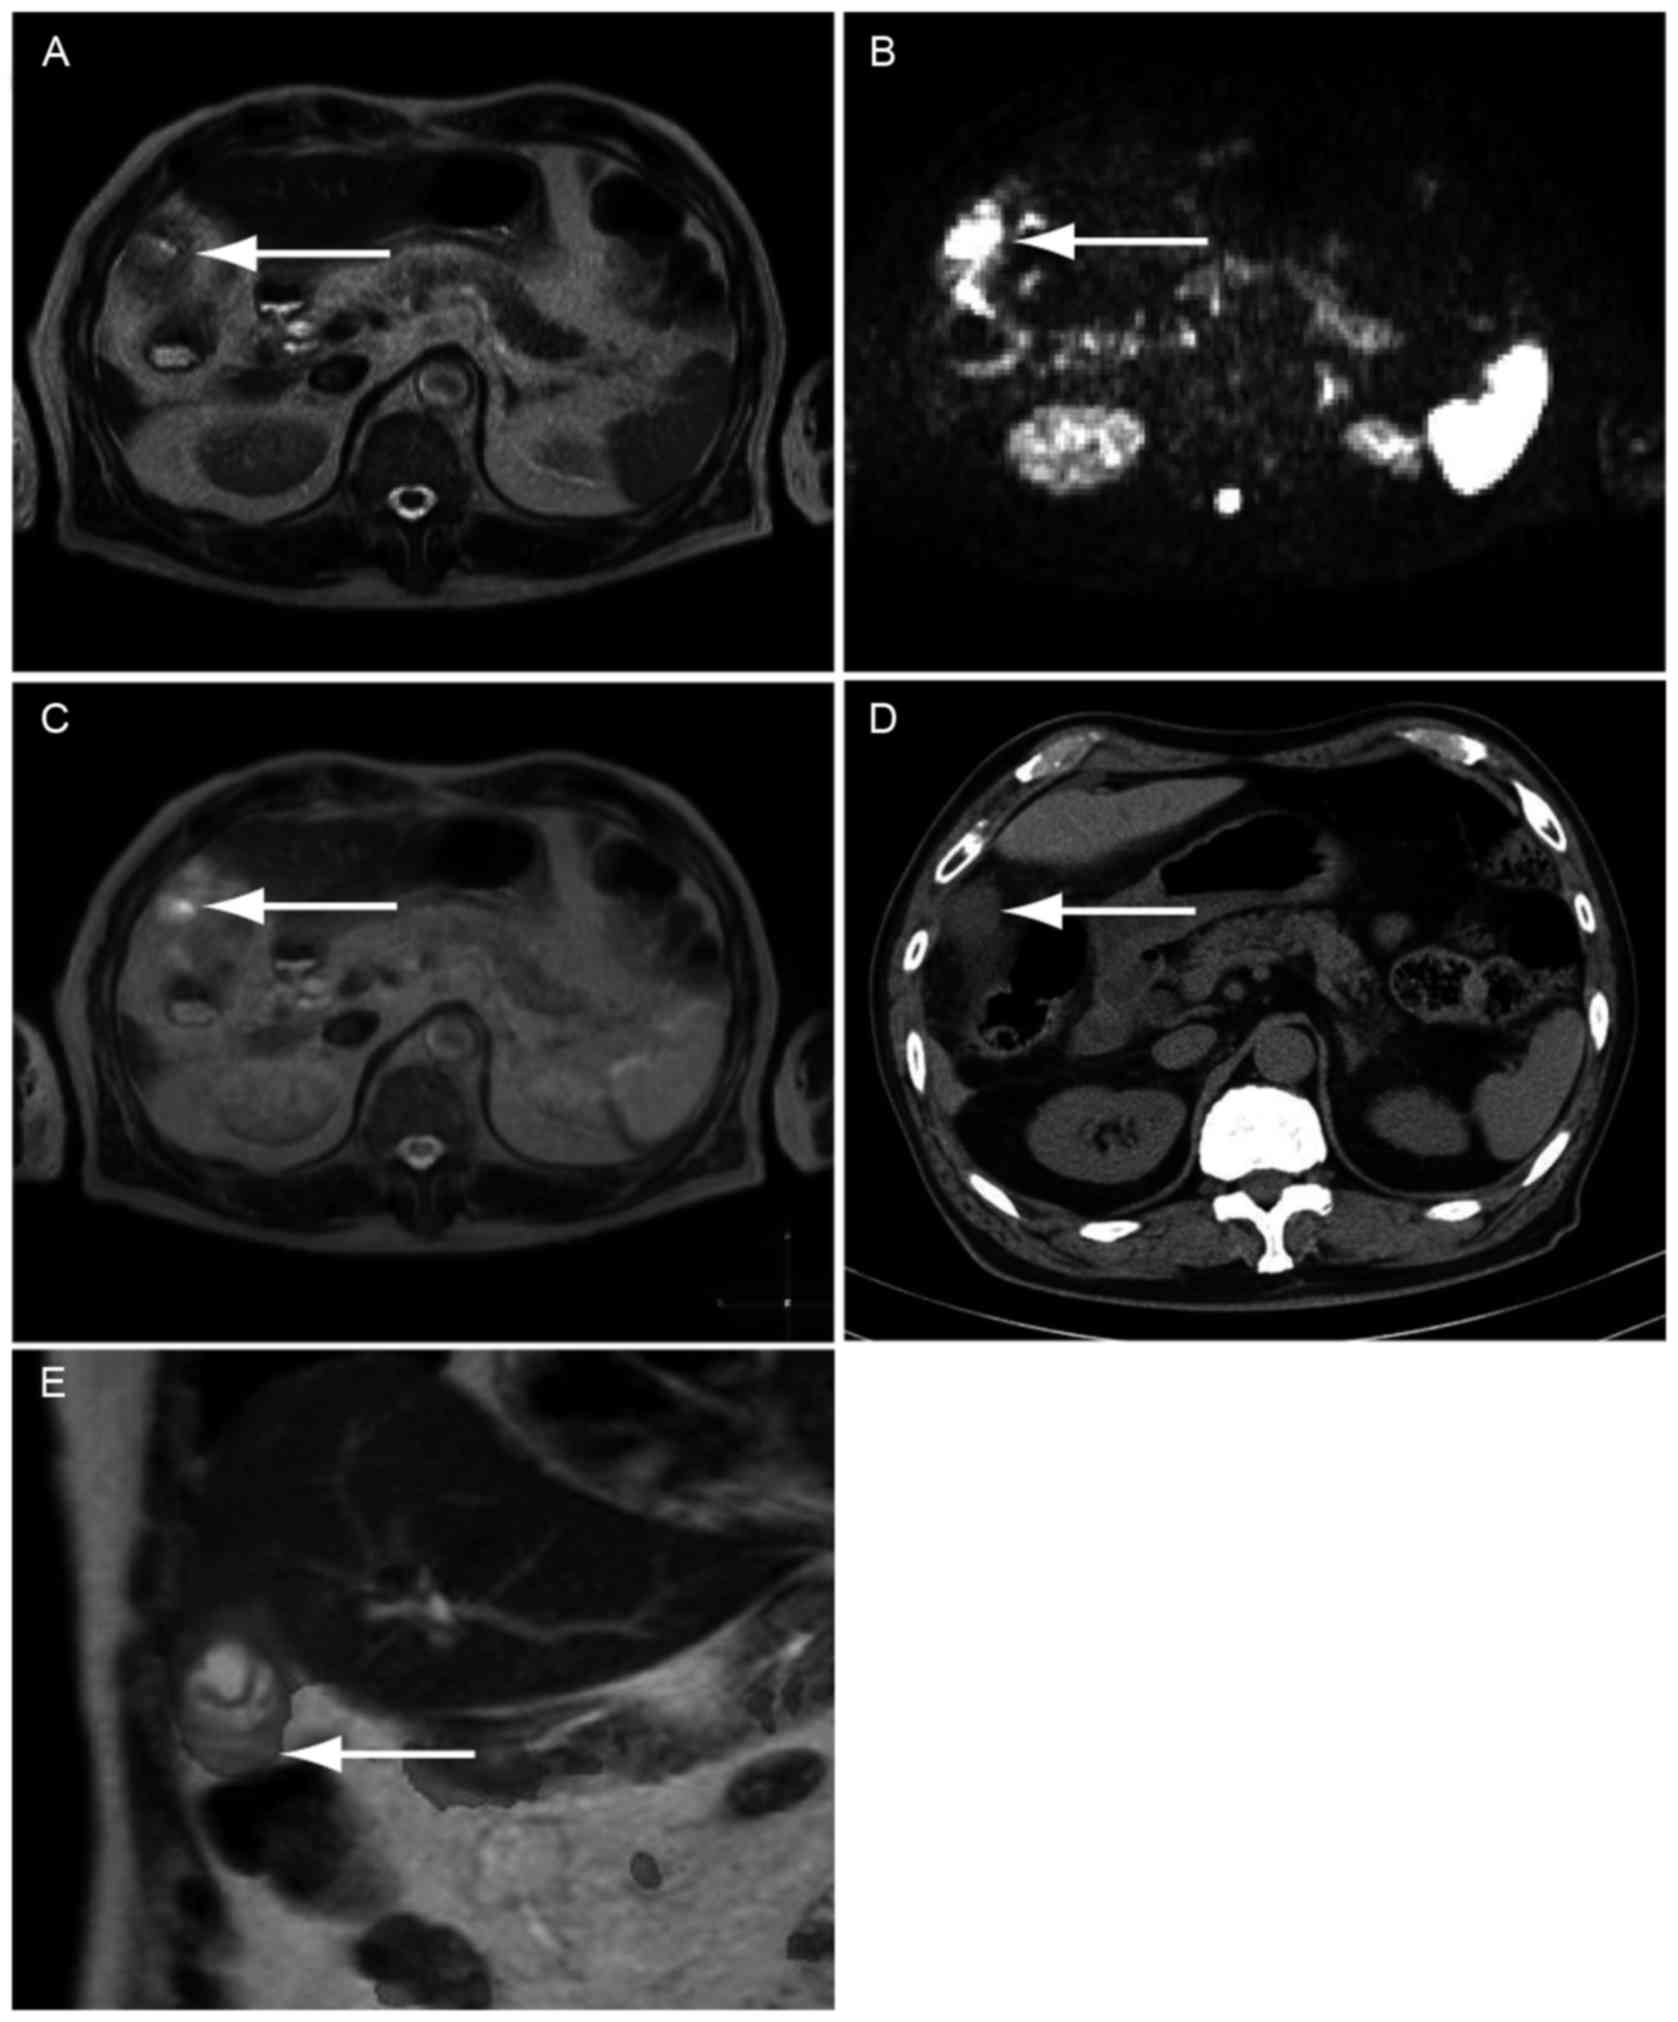

Unusual Presentation Of Pancreatitis With Extrapancreatic

Unusual Presentation Of Pancreatitis With Extrapancreatic